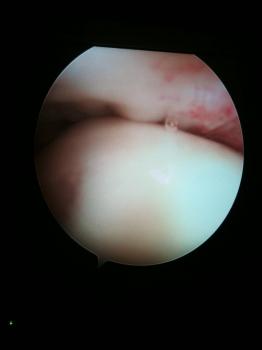

Elle est classiquement réalisée sous arthroscopie, c’est à dire à l’aide d’une caméra vidéo et de petits instruments. Cependant, la chirurgie avec une incision plus importante peut être réalisée dans différents cas.

Le geste chirurgical consiste à enlever une épaisseur d’os sous le dessous de l’os acromion, os surplombant les tendons de l’épaule et les comprimant. On parle de décompression. Plusieurs gestes sont souvent associés lors de la chirurgie : résection ou réparation de la longue portion du biceps (ténotomie), résection de l’articulation acromio-claviculaire, section du ligament acromio-claviculaire, de calcification.